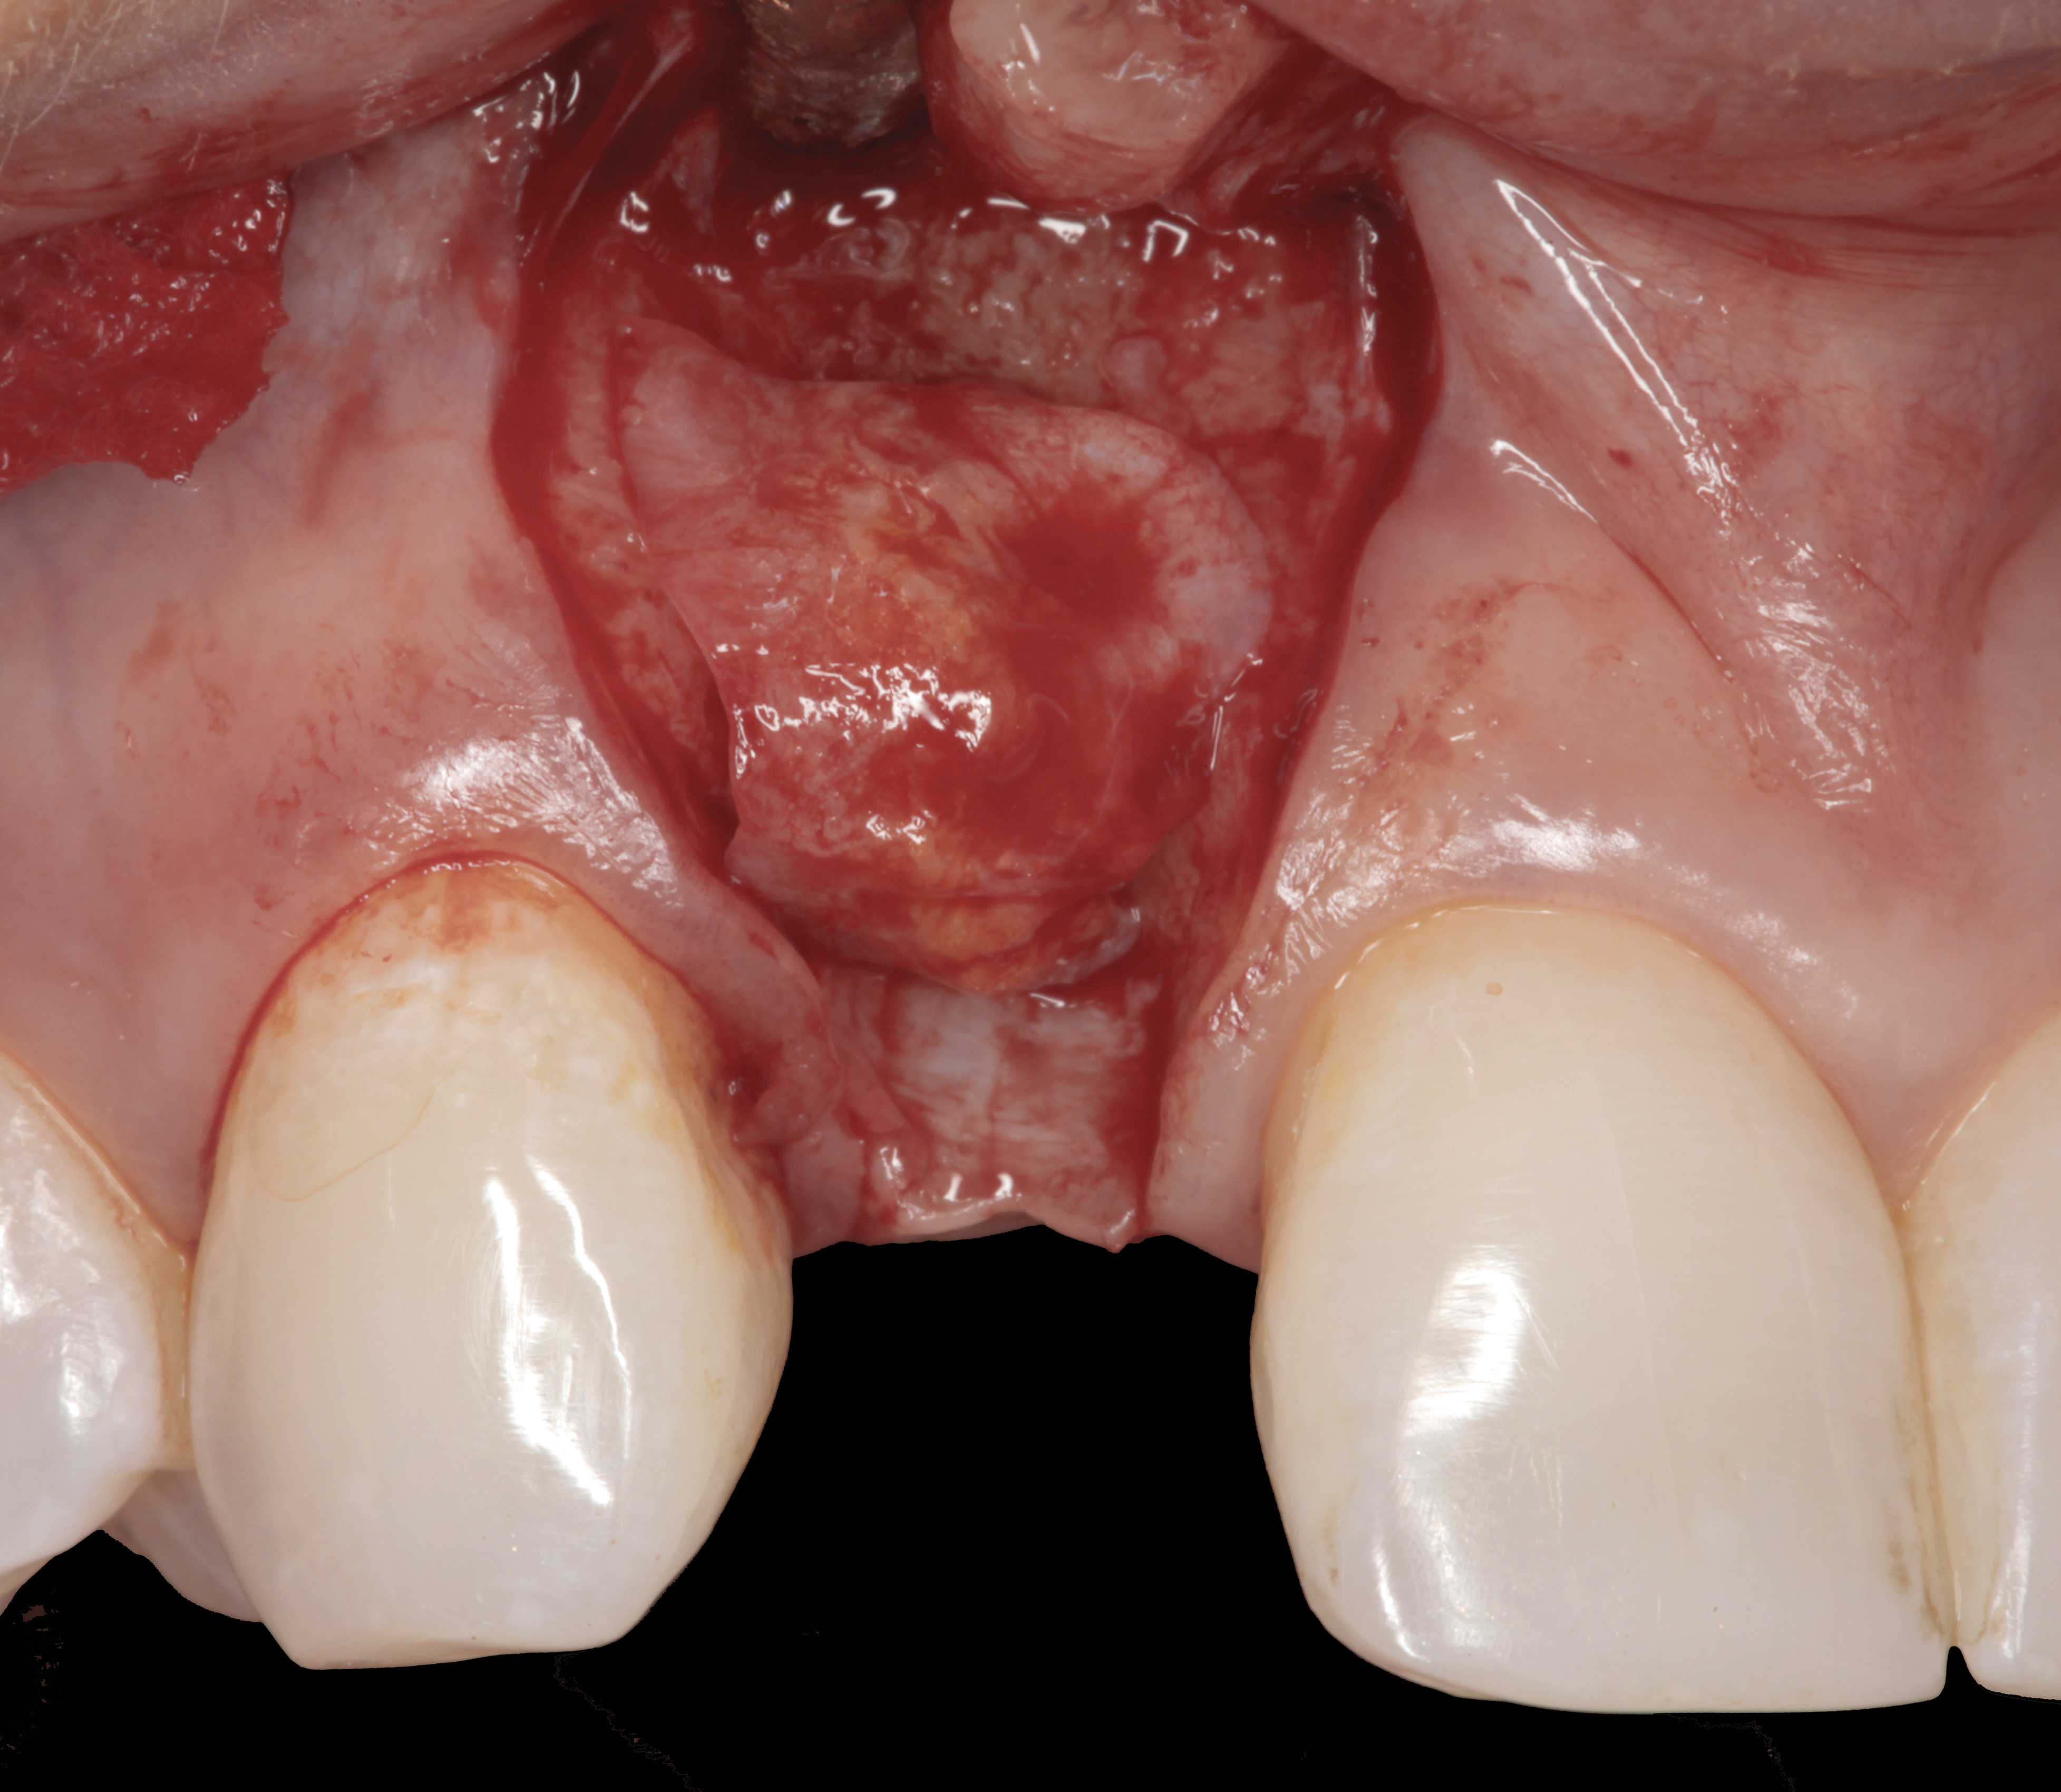

The following case report provides an example of this case scenario: A 28-year-old white female patient presented with her maxillary right lateral incisor significantly longer than the contralateral tooth following restoration of an existing crown that was 10 years old (Figure 3). The patient was dissatisfied with the esthetic appearance of the restoration due to the increased length, recession of the gingival tissues, and discoloration of the surrounding mucosa (Figure 4). Similar to case scenario No. 1, the first step in treatment was to decoronate the healthy implant by placing a flat surgical cover screw and employing a provisional resin-bonded-retained (RBR) prosthesis as a transitional fixed restoration (Figure 5 and Figure 6). The gingival augmentation in situ was allowed to take place for 2 to 3 weeks and was evaluated after that time (Figure 7).

It was determined that additional augmentation was required to increase the soft-tissue volume, so a subepithelial connective tissue graft was acquired from the palate (Figure 8),23,24 placed, and allowed to mature for at least 3 months. Second-stage implant undercovering surgery with a palatal-biased incision was performed after tissue maturation to further thicken the labial soft tissues. In addition, a flat contoured healing abutment was placed to allow the soft tissues to mature without risk of recession, and the RBR replaced (Figure 9). After 4 to 6 weeks of healing, a flat contoured screw-retained provisional restoration was inserted (Figure 10) with the proper submergence profile to restoratively sculpt the soft tissues. An implant-level impression was made and the definitive cement-retained metal-ceramic restoration fabricated and inserted (Figure 11 through Figure 13). The final esthetic outcome to restore the proper length and proportion of the right lateral incisor to match that of the contralateral incisor was accomplished using the treatment steps outlined above, where the mucosal tissues were augmented after implant decoronation (Figure 14).

Fig 8. A subepithelial connective tissue graft was placed.

Figure 8

Fig 9. After 3 months of healing, the implant was uncovered. A crestal incision was made with a palatal bias and rolled to the labial side to increase the soft tissue to the facial aspect.

Figure 9